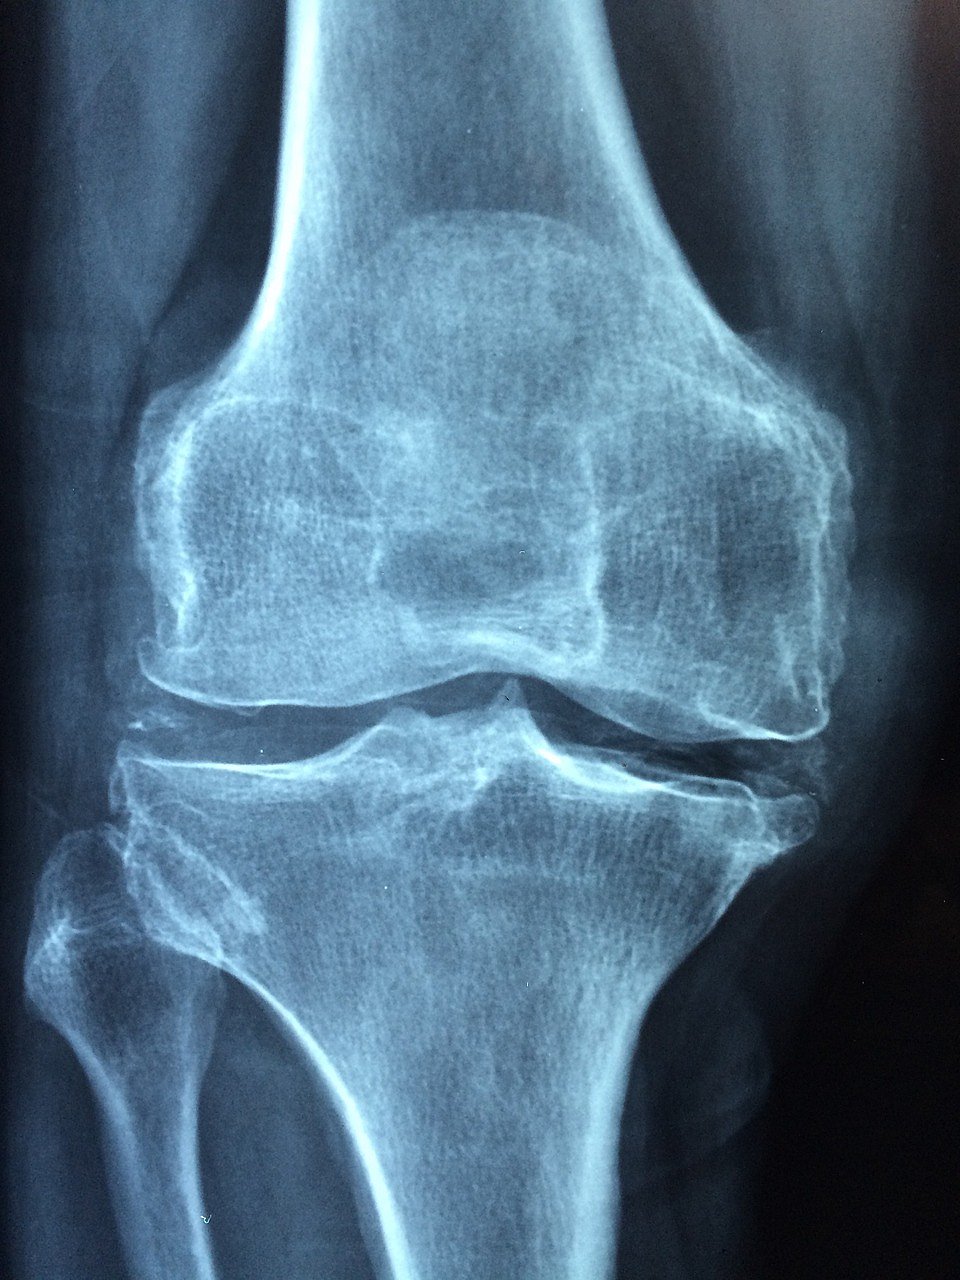

மூட்டுகளில் உள்ள குறுத்தெலும்புகள் நகரும்போது ஒன்றோடொன்று உராயாமலிருக்க அந்தப் பகுதியில் மூட்டு சவ்வில் இருந்து ஒருவித திரவம் சுரக்கும். இந்த சவ்வு வீங்கும்போதோ, குறுத்தெலும்பு சேதமாகி ஓட்டை விழும்போதோ, அதை தேய்மானம் என்கிறோம். அதனால் உராய்வு அதிகமாகிறது. அசைவு குறைகிறது. அதனால் கால்களை நீட்டி, மடக்குவது கடினமாகிறது.

முழங்கால் மூட்டு பாதிப்பு வந்துவிட்டால் முதலில் அதற்கான காரணத்தைக் கண்டறிய வேண்டும். பெரும்பாலானவர்களுக்கு மூட்டு அழற்சி எனப்படும் தேய்மானம் காரணமாகவே மூட்டு வலி வரும். வயதாக, ஆக இந்தத் தேய்மானம் ஏற்படுவது சகஜம். சிலருக்கு இந்தத் தேய்மானம் அதிகமாக இருக்கலாம், சிலருக்கு குறைவாக இருக்கலாம்.